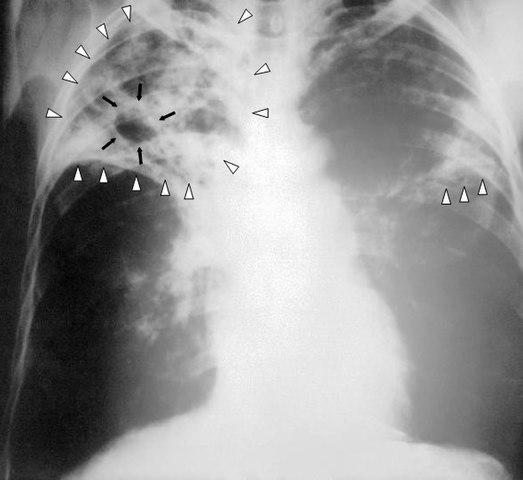

- Chest X-ray: X-rays can reveal abnormalities in the lungs.